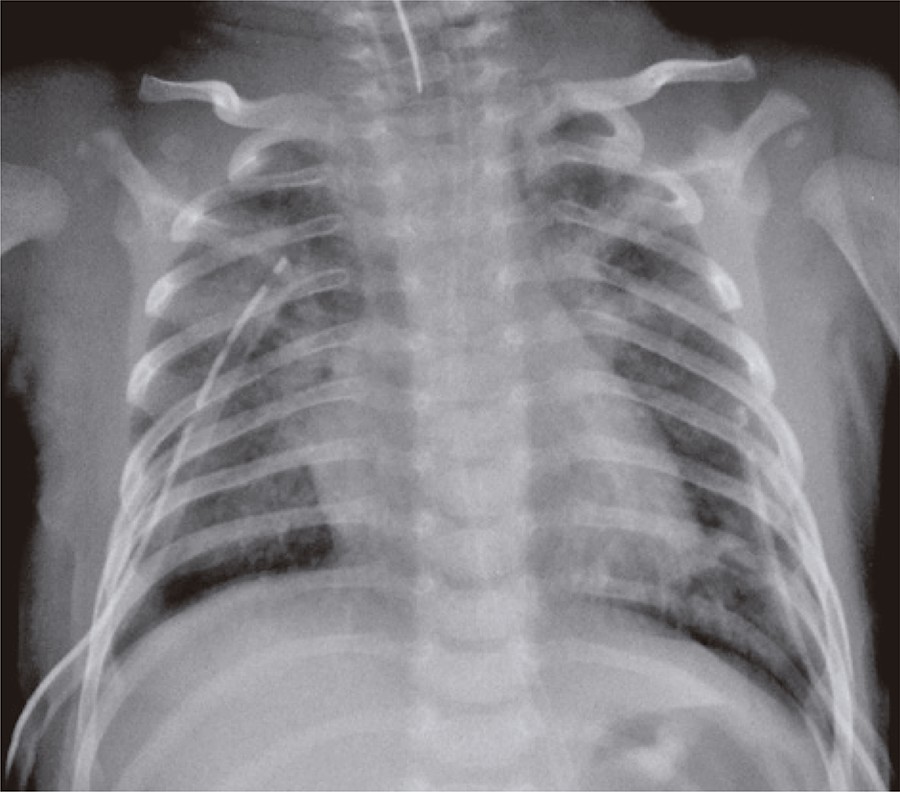

Um lactente de 37 dias de vida, do sexo masculino, previamente hígido e sem intercorrências durante período perinatal, foi admitido em unidade de terapia intensiva pediátrica com insuficiência ventilatória aguda devido à bronquiolite viral pelo vírus sincicial respiratório. Foi submetido à intubação traqueal por deterioração clínica, sendo realizada sequência rápida de intubação com fentanil, cetamina e succinilcolina. Durante o procedimento, apresentou tosse, rigidez torácica, diminuição da ausculta pulmonar e má perfusão tecidual. Persistiu com piora clínica, culminando com parada cardiorrespiratória em assistolia, revertida com compressões torácicas e duas doses de epinefrina endovenosa. Posteriormente, apresentou nova parada cardiorrespiratória, agora com suspeita de pneumotórax hipertensivo. Foi realizada toracocentese de alívio com melhora importante da ausculta pulmonar e dos sinais de má perfusão periférico. Após drenagem torácica bilateral teve seus parâmetros ventilatórios diminuídos, porém persistia com má perfusão tecidual, moteamento de pele, pulsos finos, hipotensão e ausculta cardíaca com hipofonese de bulhas. O exame radiológico de tórax confirmou pneumopericárdio hipertensivo (), resolvido com pericardiocentese e drenagem de 40mL de ar do espaço pericárdico (). O paciente teve boa evolução clínica após procedimento, permanecendo em ventilação mecânica por 6 dias e recebendo alta hospitalar em 13 dias sem sequelas aparentes.